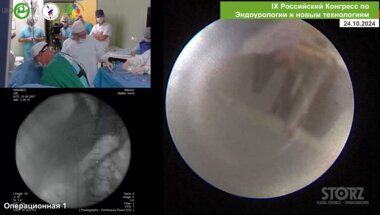

Видео спикера